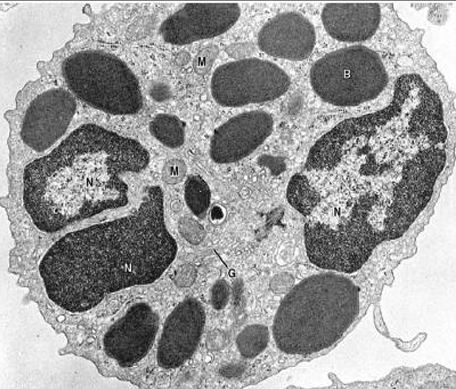

Cel. plasmática